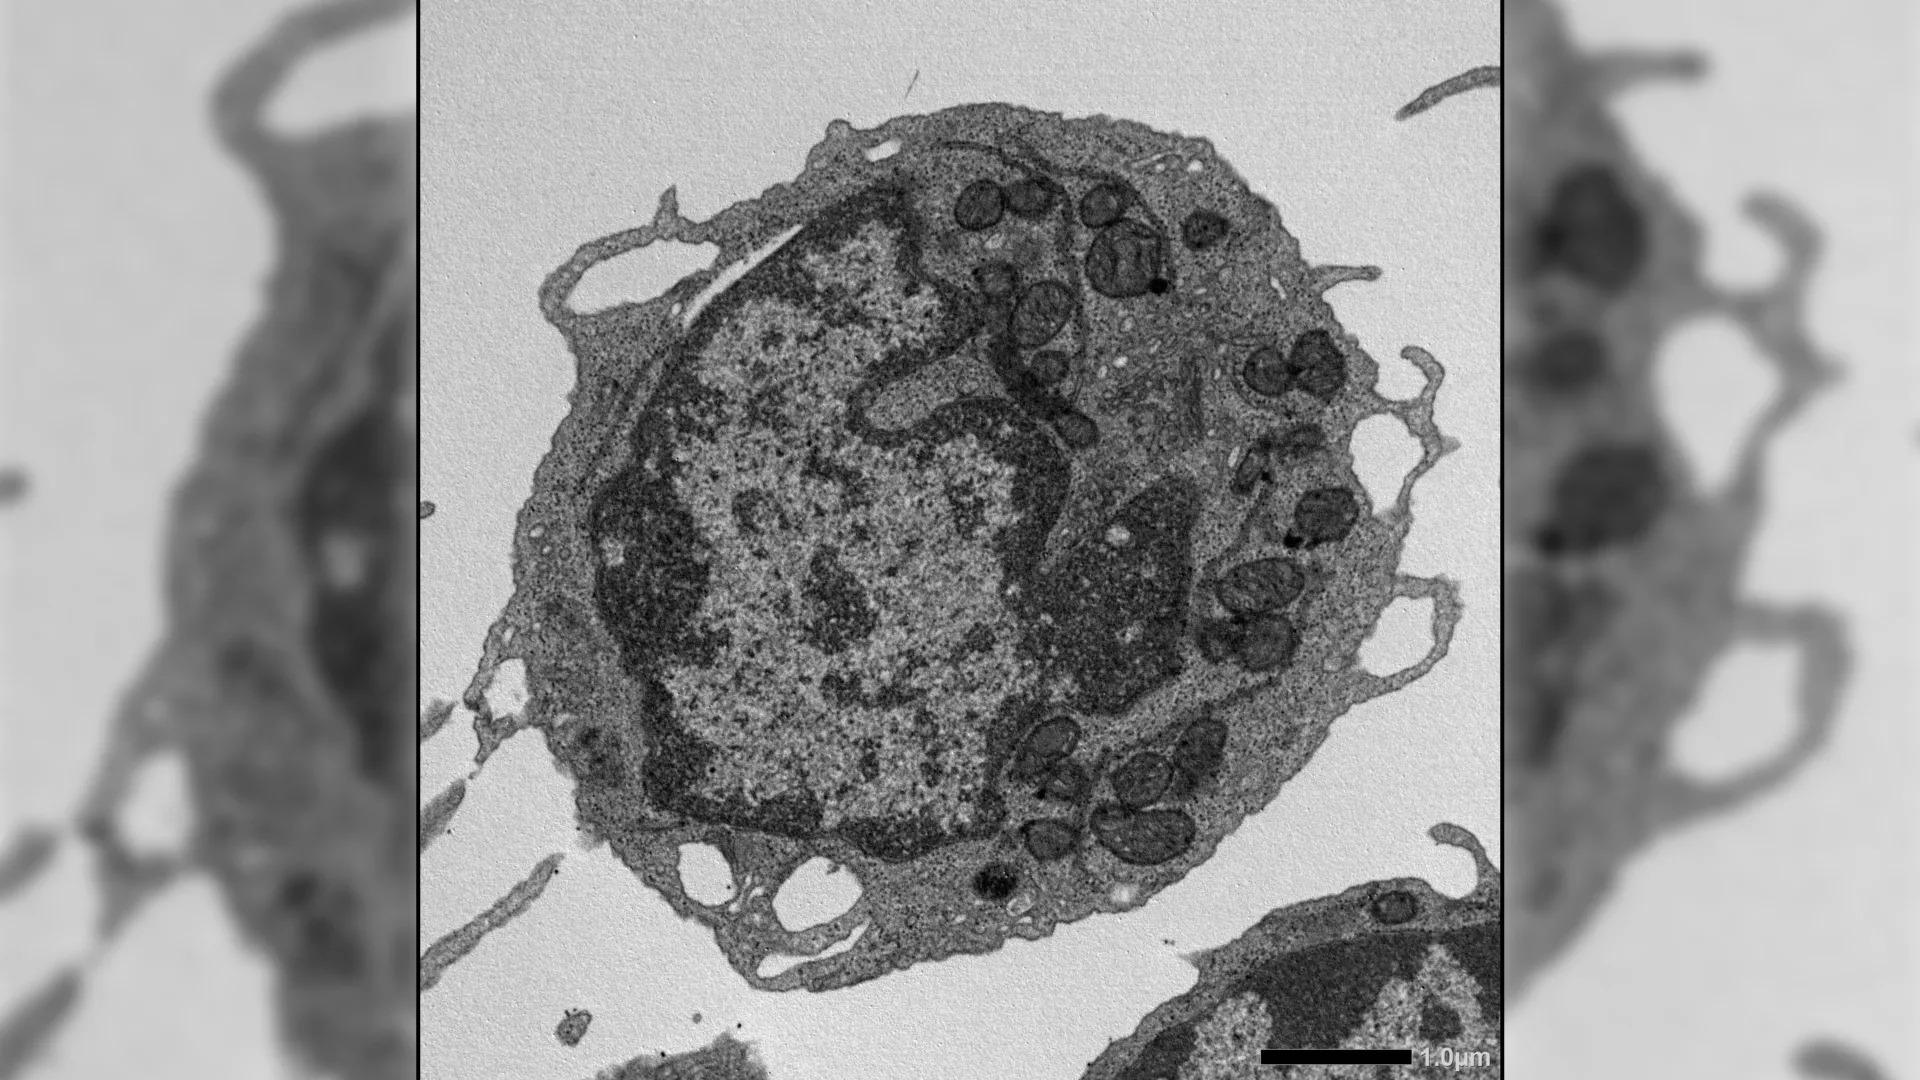

| Hình ảnh hiển vi điện tử của tế bào gốc tạo máu trên chuột. |

Khi con người già đi, hệ thống miễn dịch và máu dần trở nên suy yếu. Các nghiên cứu cho thấy nguyên nhân cốt lõi nằm ở sự xuống cấp của tế bào gốc tạo máu (HSC) được xem như nguồn sản sinh toàn bộ các loại tế bào máu trong cơ thể.

Ở trạng thái khỏe mạnh, HSC có khả năng tự đổi mới và tạo ra sự cân bằng giữa các dòng tế bào. Tuy nhiên, theo thời gian, chúng dần hoạt động kém hiệu quả, giảm sản sinh tế bào mới, đồng thời bắt đầu ưu tiên tạo ra nhiều tế bào tủy hơn thay vì tế bào lympho quan trọng của hệ miễn dịch.